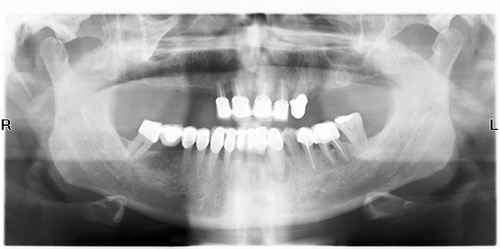

Ho consultato tramite internet lo studio Nemess-Dent in Szombathely in (Ungheria) situato a 30 chilometri dal confine con l’Austria, raggiungibile da Vienna o Bratislava. A priori, ero molto scettico, per quello che mi veniva prospetto, effettuare n. 10 impianti monofase sulla parte superiore, in poco tempo ed a costi accessibili. Non avevo sentito parlare di questo tipo di sistema. Perciò, nel mese di Maggio 2011 ho fissato l’appuntamento e mi sono recato presso lo studio Nemess-Dent per un controllo, il giorno seguente, accompagnato dall’interprete, mi sono recato nello studio dentistico, a me riservato, dove l’impiantologo, effettuando le procedure di rito, mettendomi a mio aggio, eseguendo un ortopanoramica ed accertatosi de tipo di impianti da posizione in base alla mia composizione ossea, ha proceduto all’estrazione dei denti ed al fissaggio n. 10 impianti monofase in poco più di tre ore. Successivamente, a fine dell’intervento, venivo accompagnato in albergo con i medicinali da prendere ed il ghiaccio da mettere sulle guance. Nei giorni seguenti venivo contatto dal sig. Nemess e dall’interprete se necessitavo di qualche cosa. Dopo tre giorni di guarigione, ritornavo allo studio dove mi veniva fissata una protesi in resina da tenere per sei mesi in attesa di guarigione. Nei due giorni successivi ho effettuato altre visite per vedere lo stato delle gengive e degli impianti fissati.

Prima